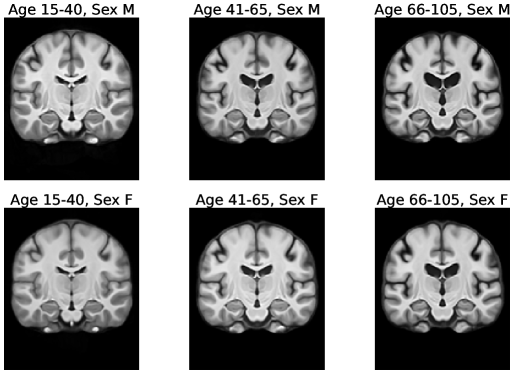

Figures 5 and 6 show visualizations for templates produced by AtlasMorph and the AtlasMorph-Uncond variants. Supplemental Figure 15, and Figure 16 show templates optimized using ANTs. The Aladdin templates are shown in Supplementary Figure 17 and Figure 18. The learned AtlasMorph templates are significantly sharper than the average of the population, shown in Figure 4.

Conditional AtlasMorph captures variability across age that a single unconditional template cannot. For example, younger subjects have more grey matter, and ventricles get larger as subjects grow older. The intensities of the atlas involve contrast changes that are consistent with segmentation boundaries, capturing the alignment between the intensity templates and the segmentation templates. We include additional visualizations of templates conditioned on age, sex and disease (cognitively normal - mild cognitive impairment - Alzheimer’s disease) in the Supplemental Material, Figure 21.

7.2 Frangmented ANTs Templates

We build the fragmented ANTs templates using the same method as the single ANTs templates. For each of our 6 templates, we sample 100 subjects from each group. Our groups are partitioned into male and female with three age groups each: 15-40, 41-65 and 66-100. The resulting templates are shown in Figure 16.